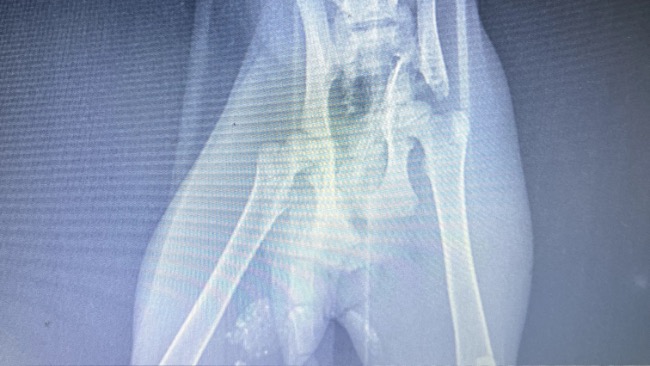

Jeszcze kilka dni temu 4-miesięczna, trzykolorowa koteczka Astra została potrącona przez samochód. Była bezradna, jej tylne łapki odmawiały posłuszeństwa. Dziś, po szczegółowych badaniach i zdjęciach RTG, wiemy już więcej – ale diagnoza ścina z nóg.

Astra wymaga skomplikowanej i kosztownej operacji miednicy.

Wciąż nie mamy pewności, czy jej rdzeń kręgowy na odcinku lędźwiowym nie został uszkodzony tak poważnie, że nigdy nie odzyska pełnego czucia w łapkach.

Dzięki naszej współpracy z gabinetem weterynaryjnym FaunaVet Astra otrzymała już wsparcie farmakologiczne i jej ból został uśmierzony. Teraz przed nią diagnostyka i badania RTG, które pokażą, jakie są rokowania.